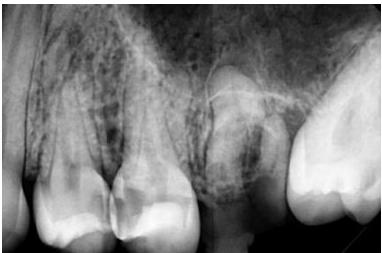

Clinical Examination

Upon clinical examination, caries were diagnosed in the distal area of tooth #24, and a deep caries lesion in the mesial area of tooth #25 was found to be causing irreversible pulpitis. In tooth #26, only a root remnant was present, and an extraction was planned. (Fig. 1 & 2)

In tooth #25, the mesial wall was first reconstructed using the same technique, leaving the central portion of the cavity open to facilitate the root canal treatment (Fig. 3). Root canal treatment was then performed using the elements™ Connect and Apex Connect systems. The initial file used was Traverse Glide path file size 13/.06 (21 mm), followed by ZenFlex files 20/.06 and 25/.06 (21 mm). Sodium hypochlorite 5.25% was used as an irrigant between files, with ultrasonic irrigation and a final rinse with EDTA 17%. For canal obturation, the vertical condensation technique was employed using an epoxy-amine resin-based sealer with the elements™ IC system (Fig. 4).

The root canal treatment was successfully completed,and the patient reported relief from the spontaneous pain. (Fig. 5&6).

Fig. 1 The X-ray initially reveals the following findings: caries on the distal sur-face of tooth #24, mesial caries on tooth #25, and a root remnant associated with tooth #26.

3 Reconstruction of the mesial wall using SimpliShade prior to endodon-tic treatment.

4 Canal shaping performed with Traverse and ZenFlex files, followed by obturation using the 3D continuous wave technique.

Fig. 5 Final radiographic assessment following the composite restoration of tooth #24 (occluso-distal) and tooth #25 (occluso-mesial) using SimpliShade Medium.